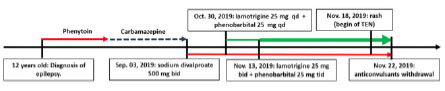

The Sixteen-year-old girl, who presented epilepsy from 12 years old, treated with phenytoin, and afterwards carbamazepine. Because of persistent seizures, on September 03, 2019 she was turned to sodium divalproate 500 mg 1 tablet every 12 hours PO. On October 30, 2019 lamotrigine 50 mg ½ tablet every 24 hours and phenobarbital 100 mg ¼ de tablet every 24 hours PO were added. Two weeks afterwards, doses were increased: lamotrigine 50 mg ½ tablet every 12 hours and phenobarbital 100 mg ¼ tablet every 8 hours. On November 18, 2019 she began with an erythematous itchy rash on face, then it spread to the entire surface area. On November 22, she was admitted in a private hospital, where betamethasone 7mg every 24 hours EV and cetirizine/pseudoephedrine 10/120 mg every 24 hours PO was administered, and anticonvulsants were withdrawn. In the day following, mucocutaneus lesions got worse. Then this patient was transferred to our hospital, being admitted on November 28, 2019. Figure 1 shows a time line of the drugs taken by the patient.

Figure 2 Day of admission (November 28, 2019). Morbilliform and erythematous rash involving more than 90% of the body surface with sloughing of the lips and nostrils (A-C). Bloated face; dry mucous membranes, erythematous, fissured and bleeding lips; and limitation of mouth opening (A-C).